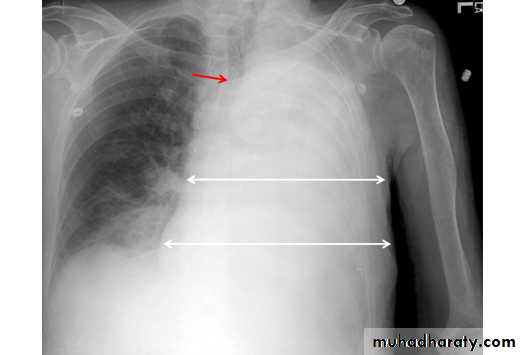

48.opasified hemi thorax Total collapse

Homogenus opacity of the right hemithorax with shifting of the trachea to the same side48.opasified hemi thorax Total consolidation

Homogenus opacity of the left hemithorax with central trachea

Total collapse

Homogenus opacity of the left hemithorax with shifting of the trachea to the same sidePleural effusion

Homogenus opacity of right lower zone with meniscus signOblitration of right cardiophrenic and costophrenic angles

Homogenus opacity of the right hemithorax

Oblitration of cardiophrenic and costophrenic angles

Shifting of the trachea to the opposite side

Pleural effusion

Homogenus opacity of right lower lobe with Oblitration of right cardiophrenic and costophrenic angles.

Meniscus sign